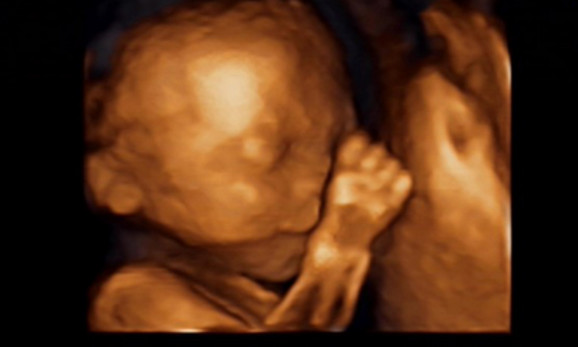

27岁的曹女士,已经怀孕六个月了。三天前,“孕味十足”的她,在丈夫的陪同下来到医院,准备进行提前预约好的四维彩超检查。但是万万没想到,检查结果让她的心情一下跌入低谷!通过影像显示,胎儿嘴唇中间竟然有一指宽的裂痕。经过医生再次仔细确认,腹中的胎儿确实患有唇腭裂,也就是“兔唇儿”。

唇腭裂患儿,是由于牙槽突间骨组织的缺失,造成上颌牙弓的完全性丧失,鼻基底部塌陷,牙槽突裂隙部恒尖牙萌出受阻。胎儿出生以后,需要通过牙槽突植骨术来完成唇部整形。手术具体怎么做,什么时候做,要做几次,这些都要根据孩子的具体病情。至于是否要生出来,这个就要由孕妇及家人自己决定。